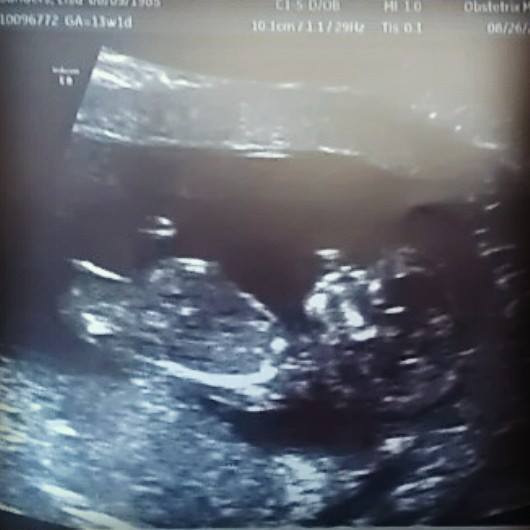

I had my NT scan at 13 weeks and 1 day and got a good nub shot. I'm curious to see what you guys guess even though I went and had a elective ultrasound done at 15 weeks and 3 days and got a confirmation from the tech. Although she said it is what I want it to be I can't help but think she might be wrong. Let me hear your guesses and then I will tell you what she said! :)

Attachment 14092